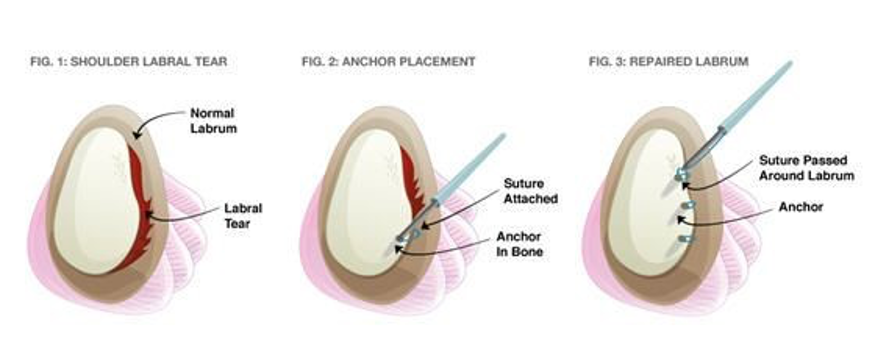

Se la lesione interessa quasi esclusivamente i tessuti molli come il cercine o i legamenti si opta in genere per un approccio in artroscopia: tramite piccole incisioni cutanee si inserisce nella spalla una telecamera ed alcuni strumenti per poter effettuare la riparazione delle strutture danneggiate.

Questa tecnica, chiamata Capsuloplastica artroscopica, si avvale dell’utilizzo di piccole ancorette che vengono fissate alla glena dalle quali escono dei fili ad alta resistenza che servono per la sutura del cercine e della capsula, in modo da ricreare la giusta contenzione della testa dell’omero all’interno dell’articolazione.